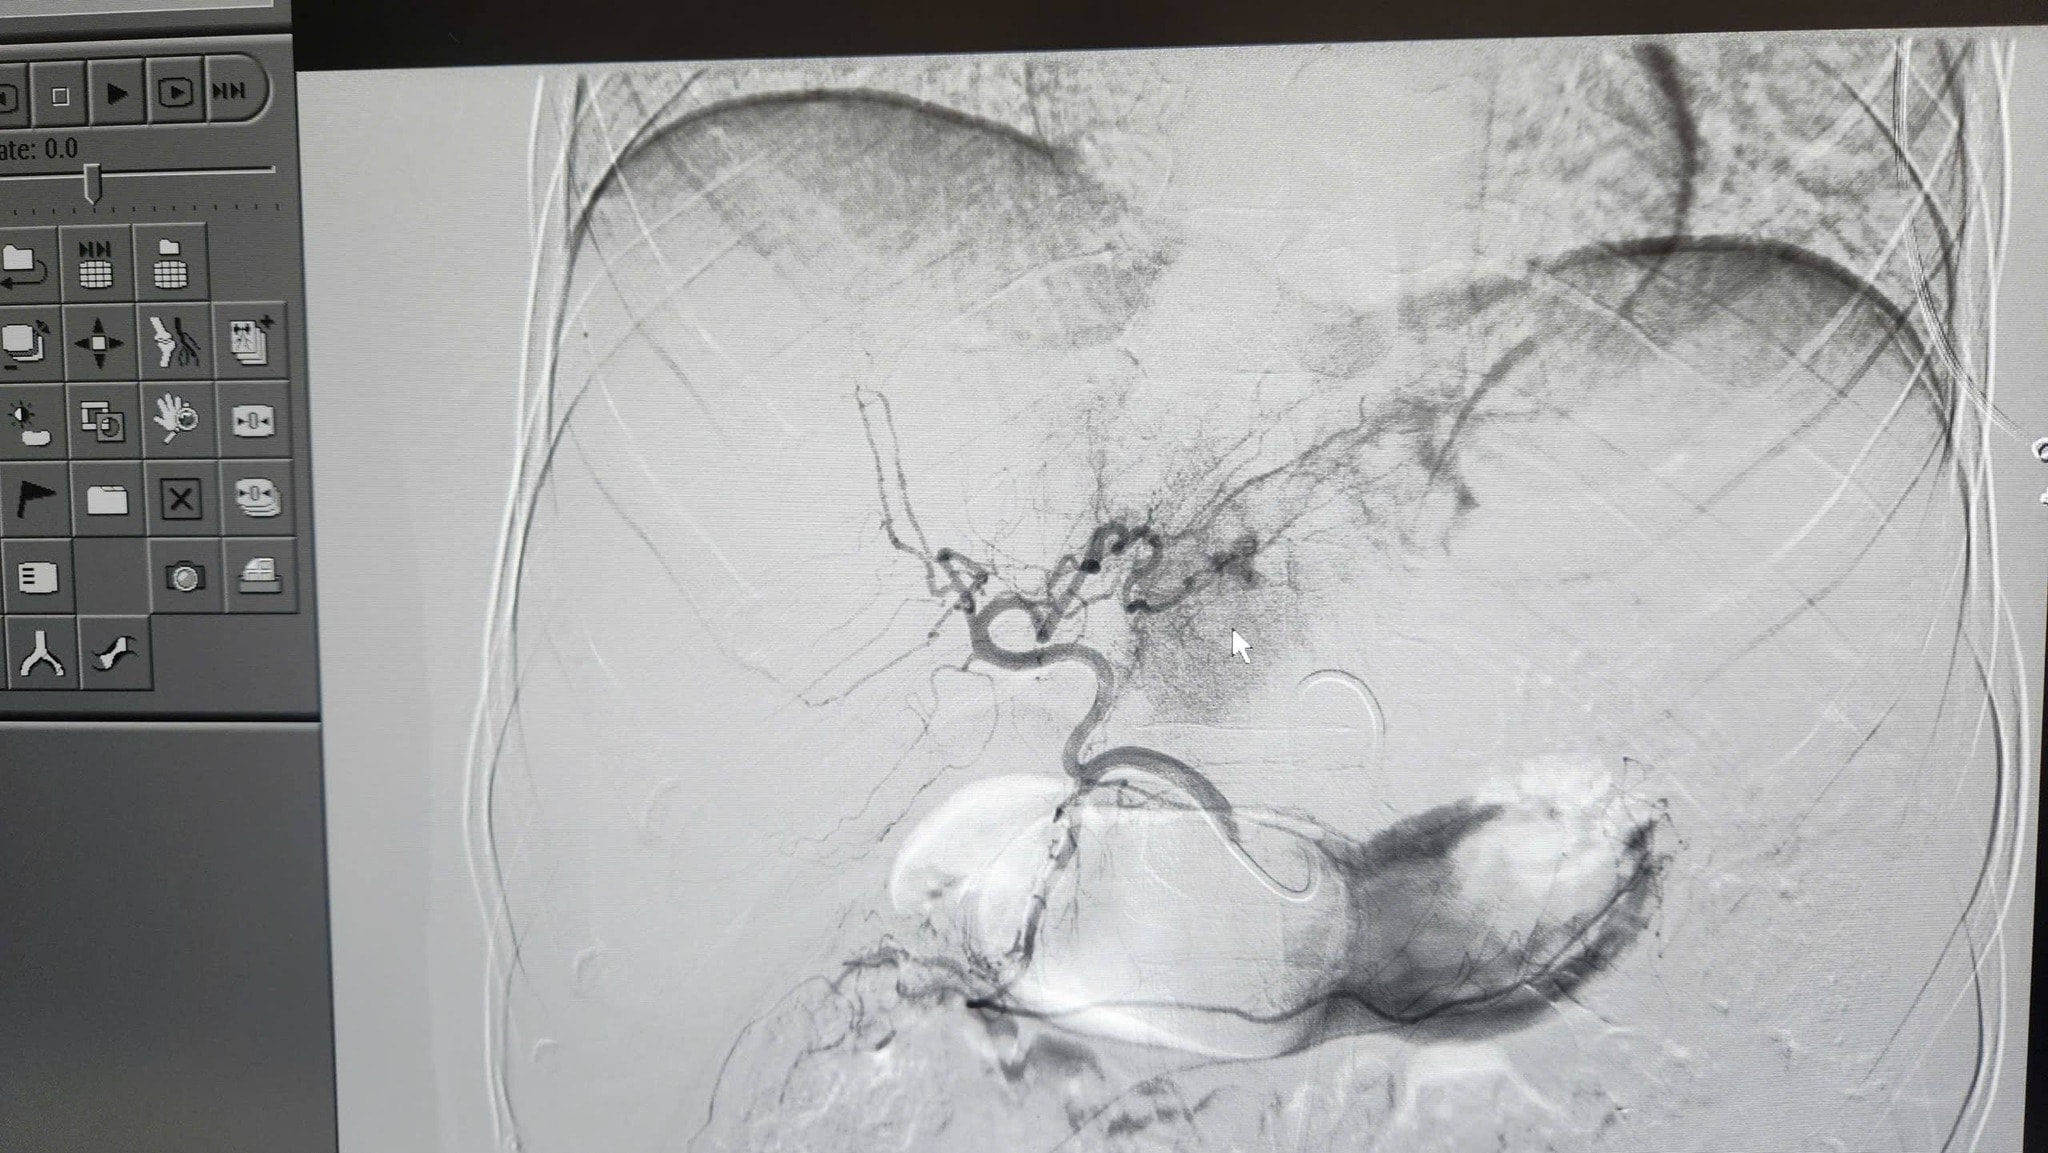

Hình ảnh lá gan bị vỡ của bệnh nhân. Ảnh: BVCC

Ê-kíp can thiệp mạch do BSCKII Ngô Vĩnh Hoài - Phó Trưởng khoa Chẩn đoán hình ảnh trực tiếp thực hiện. Dưới sự hỗ trợ của hệ thống chụp mạch số hóa xóa nền (DSA) hiện đại, các bác sĩ đã thao tác chính xác, kiểm soát hoàn toàn điểm chảy máu và cầm máu hiệu quả cho người bệnh.